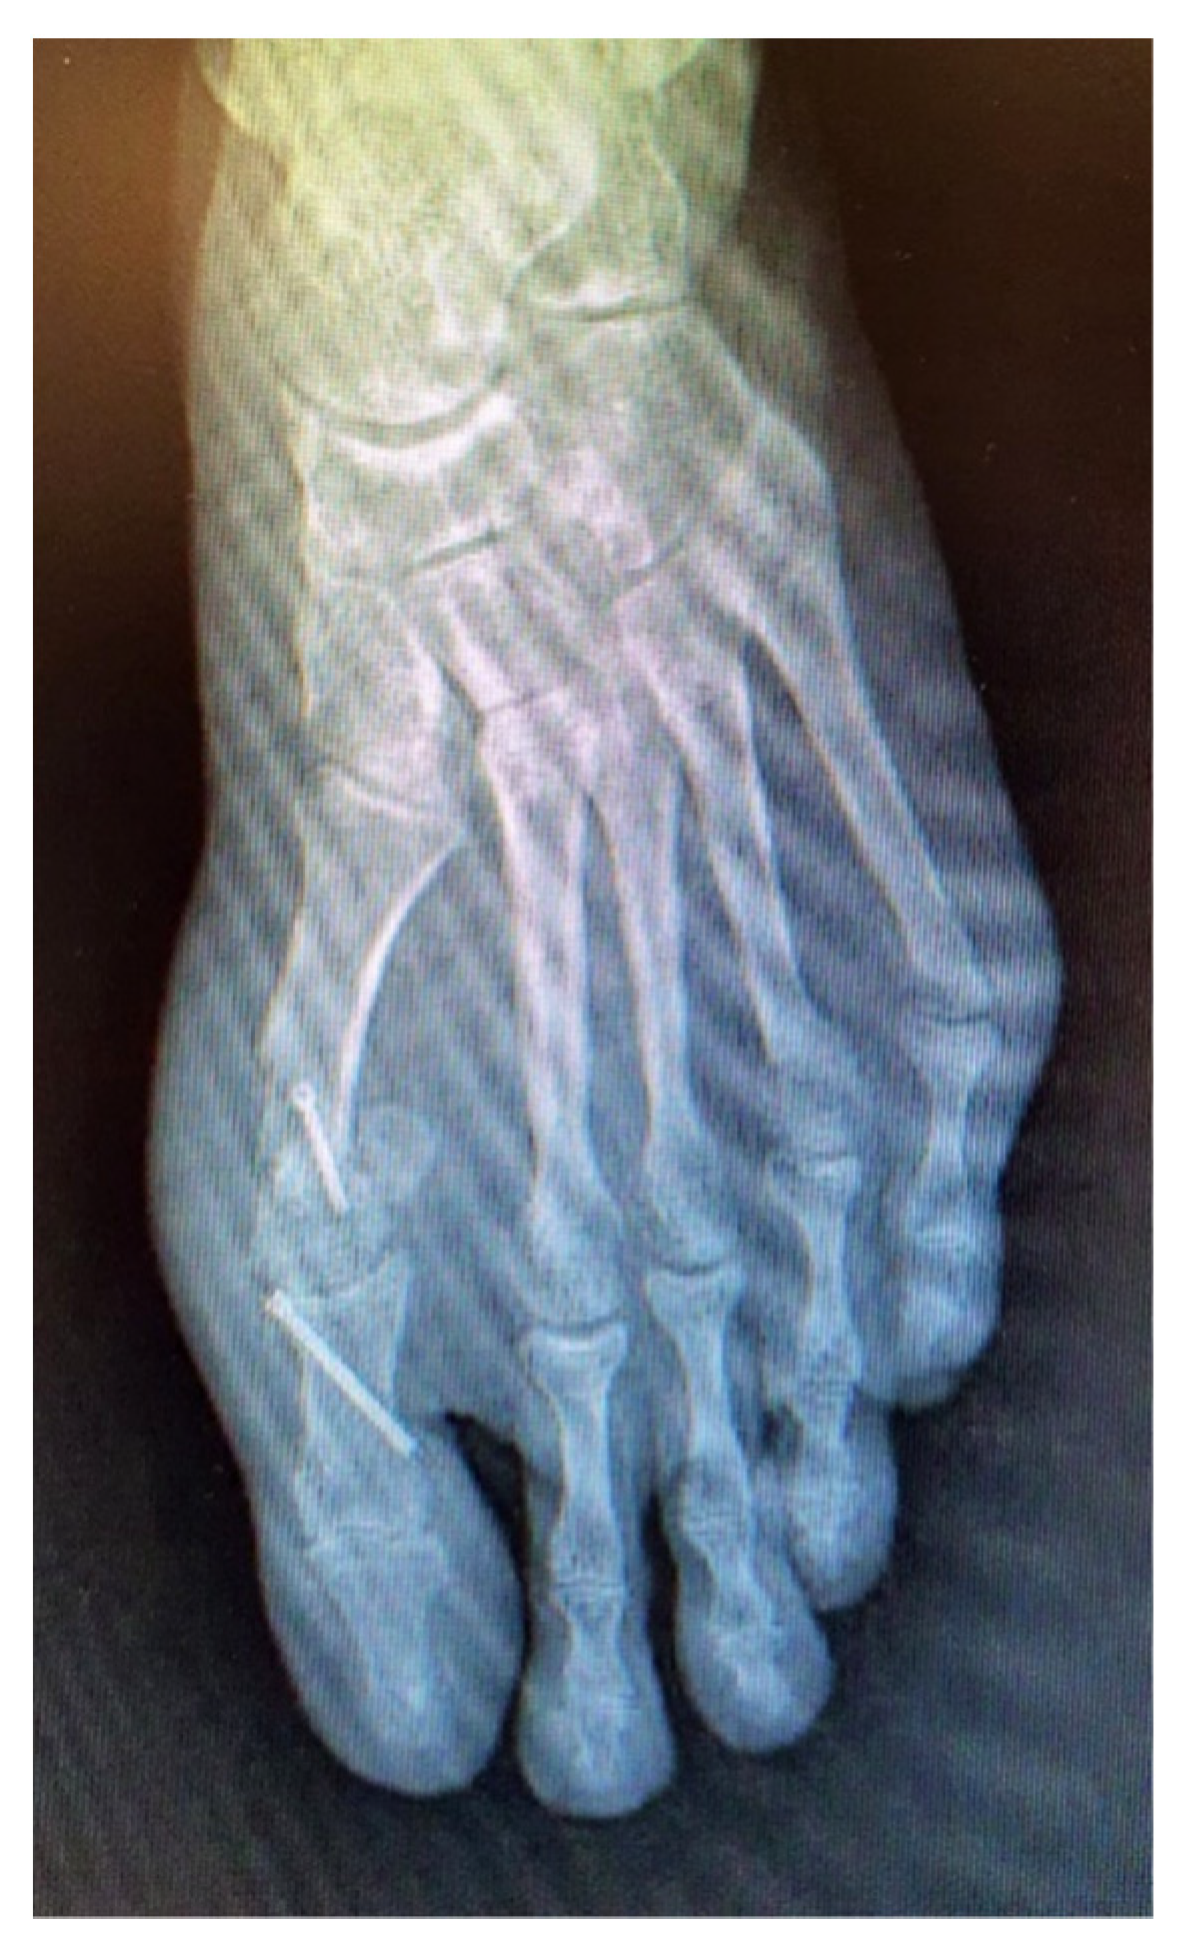

Our radiographic examination showed signs of severe joint destruction compatible with resection arthroplasty at the level of the MPJ with significant shortening of the first toe (Figure 5). The patient was treated conservatively with orthopaedic insoles.

Figure 5. Postoperative radiography after second surgery. Signs of severe joint destruction compatible with resection arthroplasty.